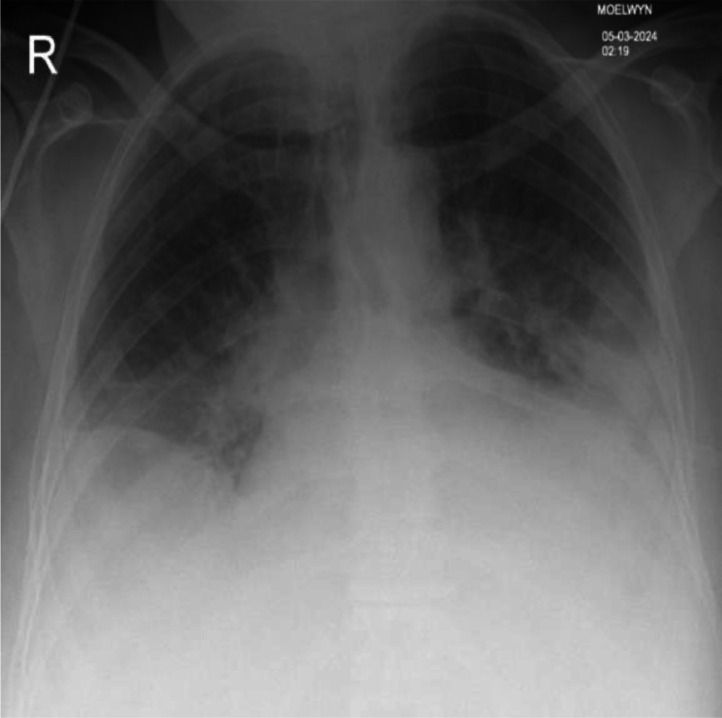

Scrub typhus, caused by Orientia tsutsugamushi, is a rickettsial infection transmitted by mite bites, often underdiagnosed in travellers from endemic regions. This case report describes a 65-year-old female with hypertension who developed severe scrub typhus after a trip to Sri Lanka. She presented with fever, myalgia, headache, fatigue and a scabbed lesion. Initial tests showed neutrophilia, lymphocytopenia and elevated liver enzymes. Malaria was ruled out, and empiric treatment with intravenous Tazocin was initiated. On day 5, she developed Clostridium difficile infection, requiring a switch to oral vancomycin. By day 5, her condition worsened with hypoxia, hypotension, oliguria and renal failure. Chest X-ray revealed bilateral infiltrates and subsequently, she was transferred to critical care. Tests showed positive IgM test for O. tsutsugamushi. Oral doxycycline was started, resulting in rapid improvement. PCR confirmed scrub typhus. This case underscores the importance of early diagnosis and treatment with doxycycline in travellers from endemic areas presenting with febrile illness.